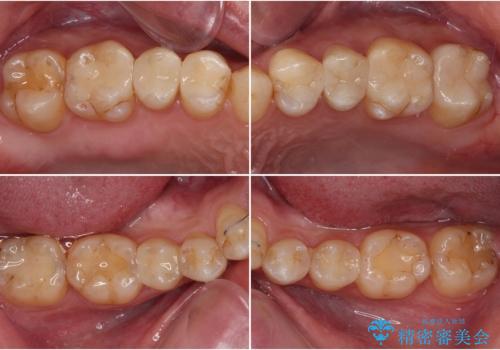

修復治療後に細かい部分をインビザラインで再度仕上げるプランとしました。

銀歯のセラミック治療が1番の希望であったため、ここまで歯列がきれいに整うとは思ってなかったようで、大変喜んでいただけました。